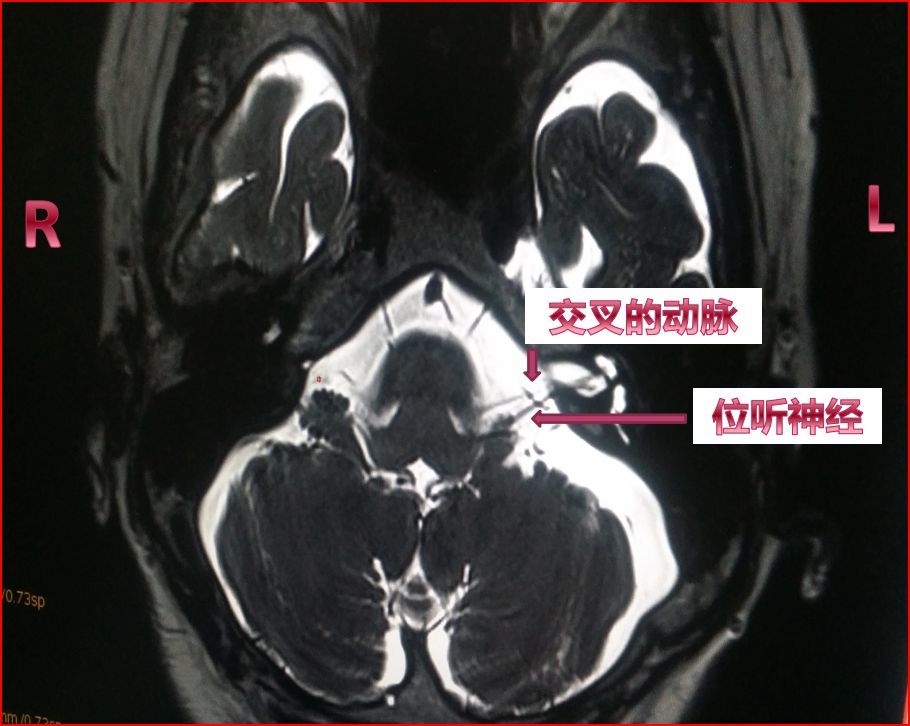

话说近两月,冯奶奶的头晕病犯得越来越频繁了。虽然每次还是几秒钟,但是呢,头晕发作时伴随了耳鸣,感觉听力也不好了,每天能发作几十次,有好几次差一点摔倒。冯奶奶的家人又带她看了几家大医院还是没法确诊。后来,家人上网查到北京朝阳医院刘明勇主任是眩晕方面的专家,就带冯奶奶千里迢迢赶到北京找了刘主任。经过详细检查又拍了特殊的内听道核磁共振,刘主任发现折磨冯奶奶的眩晕症是一种比较少见的疾病,它的名字叫--前庭阵发症。这种病是由于血管压迫了第八对脑神经所致。正常人的血管也可能会接脑神经,但是正常人的血管是柔软的,不容易对脑神经造成伤害。当年龄增大,高血压、高血脂、高血糖导致动脉硬化。变硬的血管就会反复磨蹭神经,时间久了就会磨透神经外面包裹的绝缘层包膜,第八对脑神经就象剥掉了绝缘层胶皮的电线一样裸露在外,一旦血管压迫刺激就会放电,带给人的感觉就是突然晕一下。由于第八对脑神经叫位听神经,既传递位置平衡感觉,也传递听觉,所以受刺激时除了头晕还可能会伴随耳鸣,时间久了还会出现听力下降。